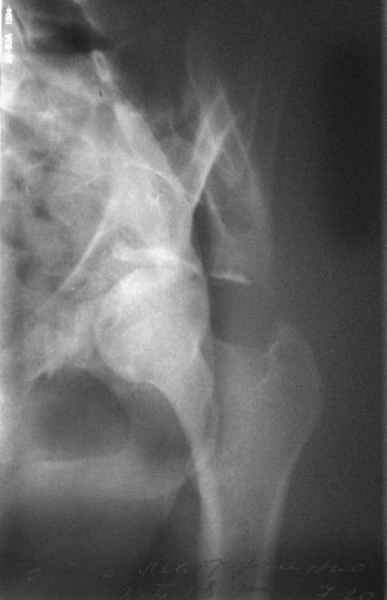

Посылаю схемы и 3D реконструкцию подобного повреждения. Называется он полным высоким двухколонным переломом вертлужной впадины, а "переломы крыла и тела подвздошной кости" входят в это понятие.

Вариантов остеосинтеза много (можно и не оперировть, т.к. конгруентность при таких переломах как правило сохраняется)

прикладываю схему доступа и случай.